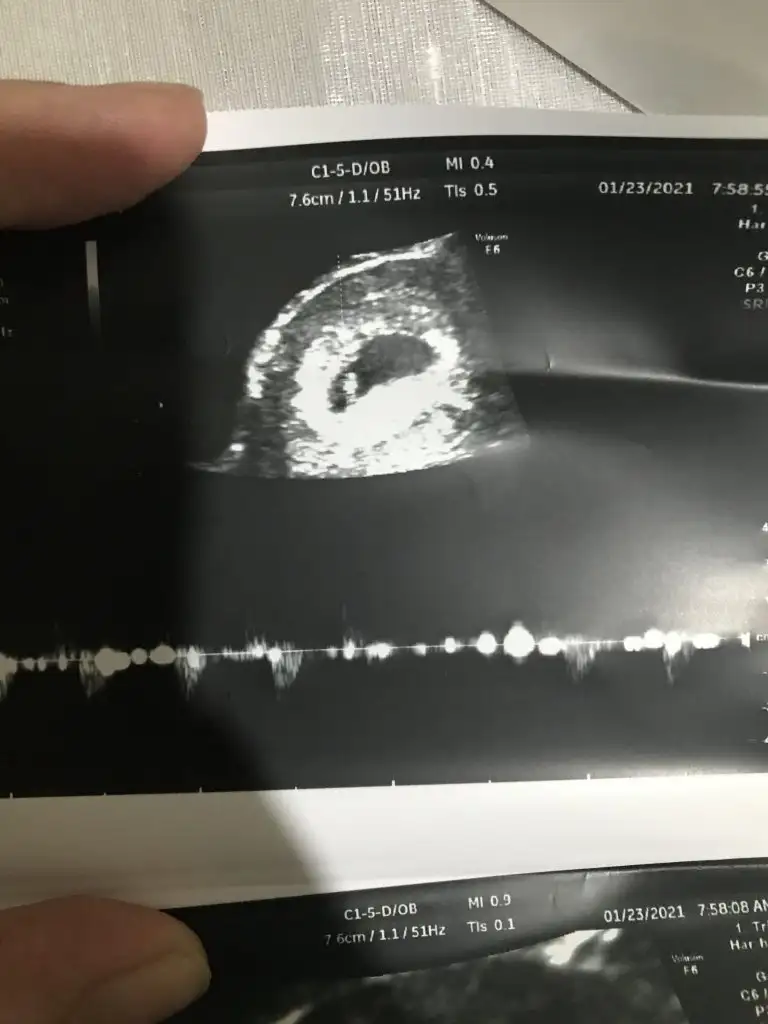

8+6 günlük cinsiyet tahmini yaparmısınız 😀😀 karından muayne resimleri

• E0495172-A4C8-4CF7-BC42-83D49B693CA3.webp

E0495172-A4C8-4CF7-BC42-83D49B693CA3.webp

46,3 KB · Görüntüleme: 196

• 58C22708-428B-4737-8308-3775BAAD2810.webp

58C22708-428B-4737-8308-3775BAAD2810.webp

52,1 KB · Görüntüleme: 163

• 6287B562-5B80-4D5D-9531-EDF1542C9421.webp

6287B562-5B80-4D5D-9531-EDF1542C9421.webp

25,8 KB · Görüntüleme: 154

• 54FFD939-75F9-47CA-B40E-B302C566F091.webp

54FFD939-75F9-47CA-B40E-B302C566F091.webp

46,6 KB · Görüntüleme: 238